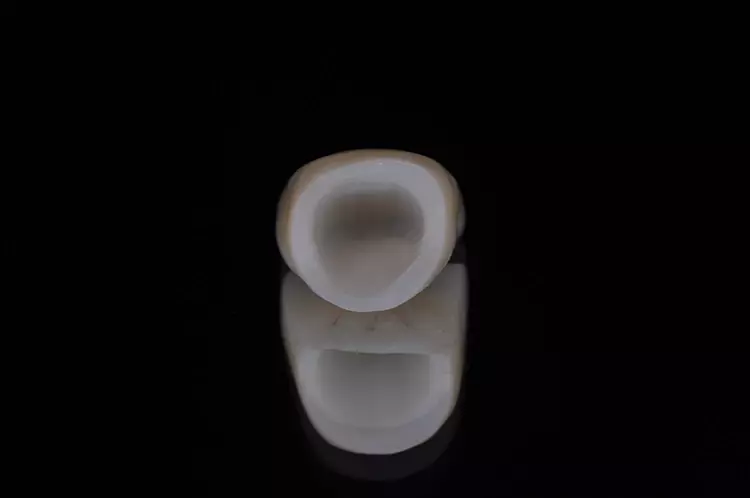

Die Auswahl des Materials für die definitive Krone wurde in Rücksprache mit dem Zahntechniker getroffen. Sie erfolgte nach der Herstellung der Arbeitsmodelle, der Beurteilung der Platzverhältnisse, der Stumpffarbe und der definierten Zielfarbe. Aufgrund des verfärbten und devitalen Zahnes und zur Vermeidung des „Grauschleiers“ galt es, ein Material mit weniger Transluzenz als Lithiumdisilikat zu verwenden.

Es sollte ein Zirkonoxidmaterial mit hochästhetischen Eigenschaften zum Einsatz kommen. Die Wahl fiel auf IPS e.max ZirCAD Prime, ein Werkstoff der zwei Zirkoniumdioxid-Rohstoffe kombiniert: im Dentinbereich ein 3Y-TZP-Zirkonia mit hoher Festigkeit (1.200 MPa Biegefestigkeit) und im Schneidebereich ein transluzenteres 5Y-TZP-Zirkonia (650 MPa Biegefestigkeit). Der stufenlose Farb- und Transluzenzverlauf in den Materialscheiben ist ein zusätzlicher Vorteil für derartige Restaurationen im sichtbaren Bereich.

Das Ausarbeiten von Details und die minimale Reduktion der Labialfläche für das Microveneering erfolgt grundsätzlich im weichen, kreideartigen Weißzustand. Das so bearbeitete und modifizierte Gerüst wird nun bei 1.530 °C gesintert und schrumpft dabei volumenmäßig um ca. 25% zum eigentlichen hochfesten Zirkonoxidgerüst.

Zur Realisierung eines möglichst naturgetreuen Behandlungsergebnisses wurde labial ein minimales Cut-back und eine anschließende individuelle Schichtung mit der Verblendkeramik IPS e.max Ceram durchgeführt (Mikroveneering) (Abb. 30–33). Damit der verfärbte Zahnstumpf unter der neuen Zirkonkrone nicht mehr sichtbar ist, wird bei transluzentem Zirkoniumdioxid im Weißzustand auf der Innenseite des Gerüstes ein Opakerliquid aufgebracht. Dieses Liquid trägt nicht auf, da das Material in den Werkstoff eindringt und das Zirkongerüst an den gewünschten Stellen von innen blickdicht, sprich opak, wirken lässt (Fa. BriegelDental) (Abb. 34 und 35).